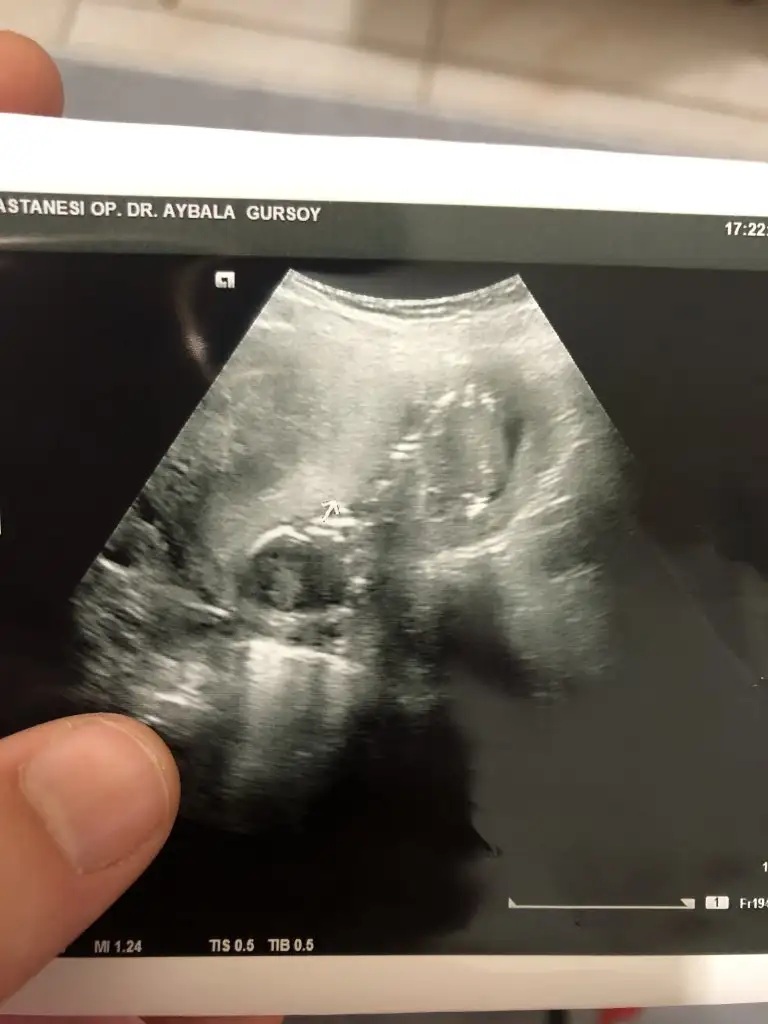

Doktor da kız gibi dedi. Teşekkür ederim. Netleşince yazarım

Teşekkür ederimKız gibi

İkra Meyra bunu da tahmin et bakalım sana zahmetIkra meyra benden biktin biliyorum ama bi arkadas uğrasmış gonderememis onun ricasi üzerine gönderdim 12+3 burda varmı bi tahmin

Evet kızım olacakOgrendinizmi kız demiştim

Sağlıkla gelsin prensesEvet kızım olacak